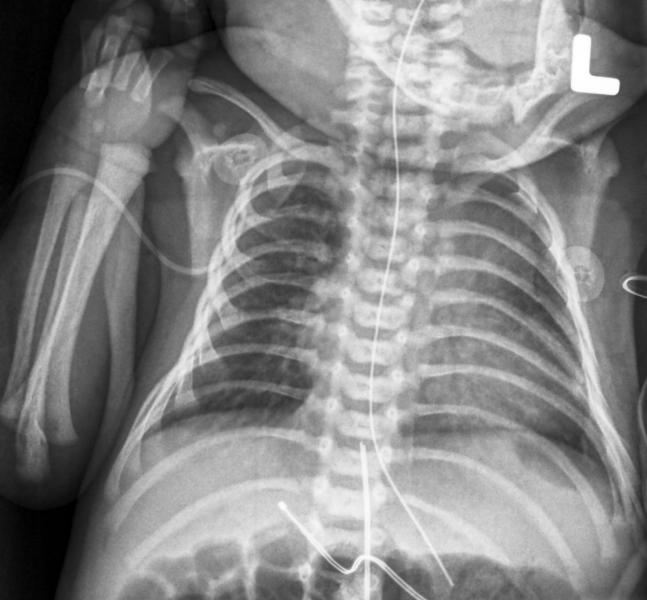

Last November, the U.S. Food and Drug Administration (FDA) issued a final guidance for medical imaging vendors on the information required in premarket notifications related to pediatric X-ray equipment. Optimizing imaging dose is particularly important for children, as their smaller size makes them more vulnerable and they are more likely to suffer long-term effects if overexposed. The guidance offers new recommendations for vendors on device labeling for pediatric use, and also covers the information that should be included in a device’s 510(k) submission and instructions for use.

The FDA guidance is intended to clarify ways that vendors can help providers optimize the delivered dose in pediatric X-ray exams. There are several factors that complicate dose determinations when it comes to pediatric patients.

The biggest challenge is determining how to segment pediatric patients for the purpose of dose calculation. Depending on the healthcare facility, “pediatric patients” are those 18 and younger, or in some places 21 and younger. Size differences complicate things further — there is greater variation in size between the youngest and oldest pediatric patients than between the youngest and oldest “adult” patients, which complicates the management of the patient dose. The dose needed to acquire an adequate X-ray is based on the size of the part of the patient being imaged, so the dose would be different between an infant and a teenager. “And how do you even quantify the size of the pediatric patient?” said Keith Strauss, MSc, FAAPM, FACR, associate professor of radiology at the University of Cincinnati School of Medicine and head of the clinical imaging physics section of the radiology department at Cincinnati Children’s Hospital. Strauss is also vice-chair of the Image Gently Alliance.

Beyond patient factors, pediatric X-ray dosing is also a function of where the exams are performed and the imaging systems used. The opening premise of the FDA guidance acknowledges that general-use X-ray imaging devices typically do not reference specific populations in the indications for use, including pediatrics, and as a result the systems may be used for any size patient. “The adult market for imaging equipment is large and the pediatric market is small,” said Strauss.

Compounding the issue of unspecified indications for use is the fact that, according to Strauss, only about 20 percent of pediatric imaging exams take place in dedicated children’s hospitals. This means that the vast majority of children are imaged in adult hospitals where the imaging systems are not adjusted to specifically meet the imaging needs of children.